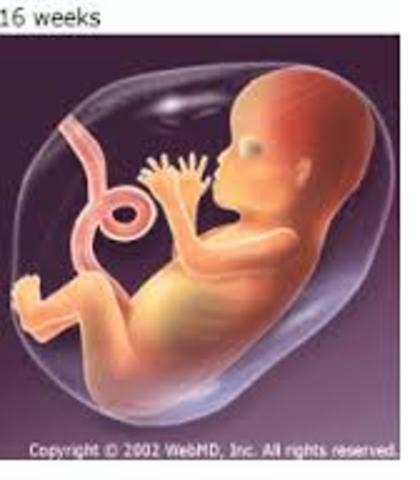

• Month IV: Baby

Month IV: Baby

~ Fetus is no bigger than a fist.

~ Males start producing testosterone, while girls produce eggs.

~ Bones are hardening at this time.

~ They practice the grasping reflex.